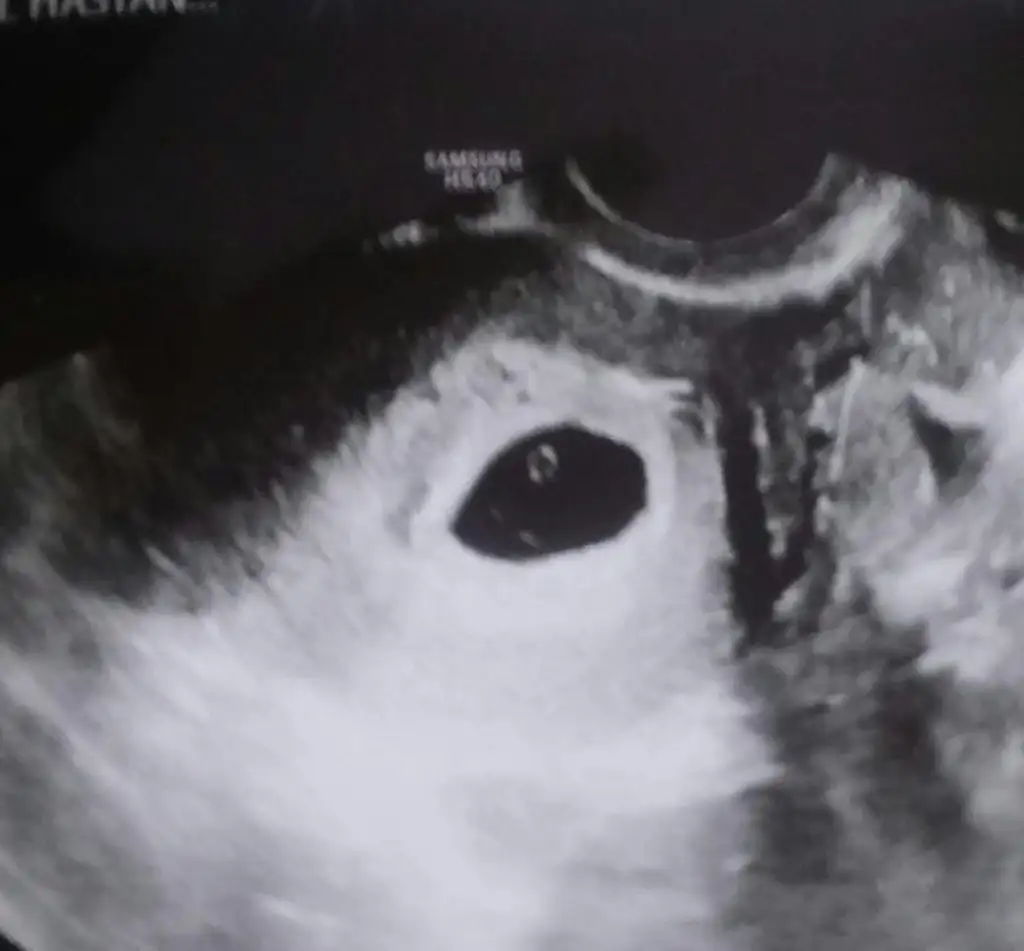

Benimde yumurtlamam 8iydi. 4 7 9 13unu degerlendirdik. Bugun akintim var baya az da kanli geliyo bi agrilarm var ama tam cozemiorm adet agrisi gibide deil boyle kasilma oluo gibi. Pilates yapiorm demistm ya karnimi iceri çekince sag kasigimn ust tarafinda agri oluyo. Pek umudum yok ama hazirlisi artik